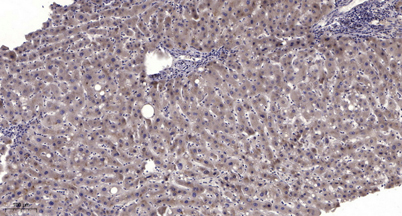

IHC

IHC-p 1:50-300